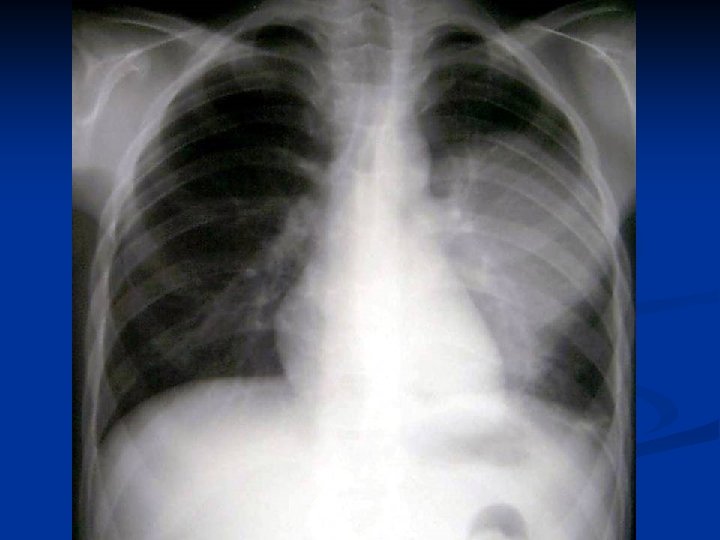

Metode de diagnosticare